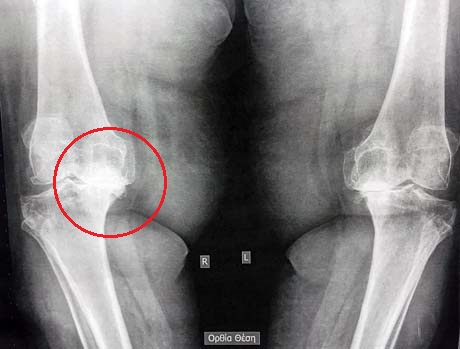

Female 67 years old with severe arthritis in his right knee and severe varus deformity (Static non loaded = 19 degrees and dynamic loaded> 25 degrees)

Patient Specific electronical preop plan. Severe non weight bearing varus deformity

Pre-op X-ray, severe osteoartrhitis of the knees bilaterally (final stage – bone to bone contact)

Varus deformity of the right knee, which reaches 17.9 degrees without weight bearing the right lower limb